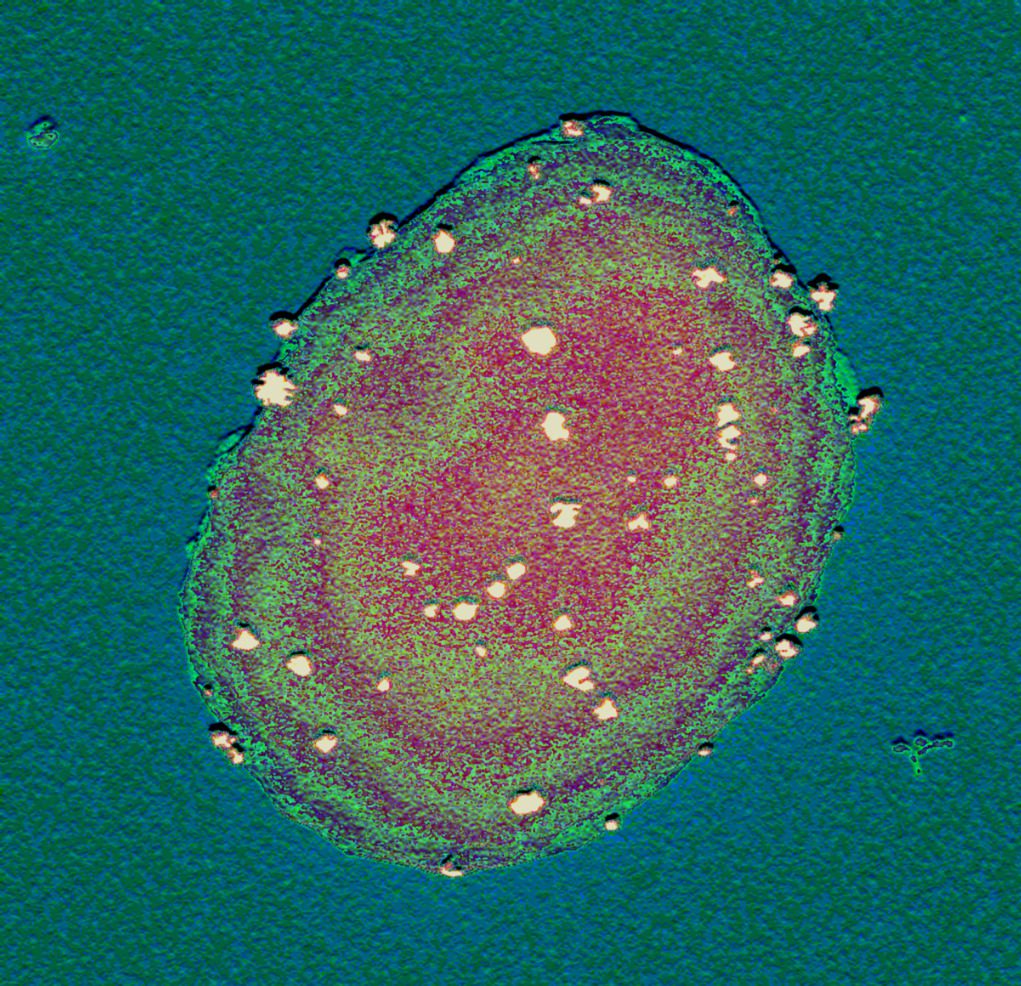

Esta área impulsa la investigación aplicada, basada en el conocimiento profundo de las características de cada individuo. Su desarrollo incluye el estudio de factores genéticos y moleculares asociados a diversas patologías, así como la influencia del microambiente donde estas se desarrollan.

El avance del Área de Medicina Personalizada se sustentará en la integración de estudios multidisciplinares combinando conocimientos teóricos y experimentales. En este contexto, el uso de herramientas in silico será clave para complementar y potenciar aquellos avances experimentales más cercanos a la aplicación clínica.